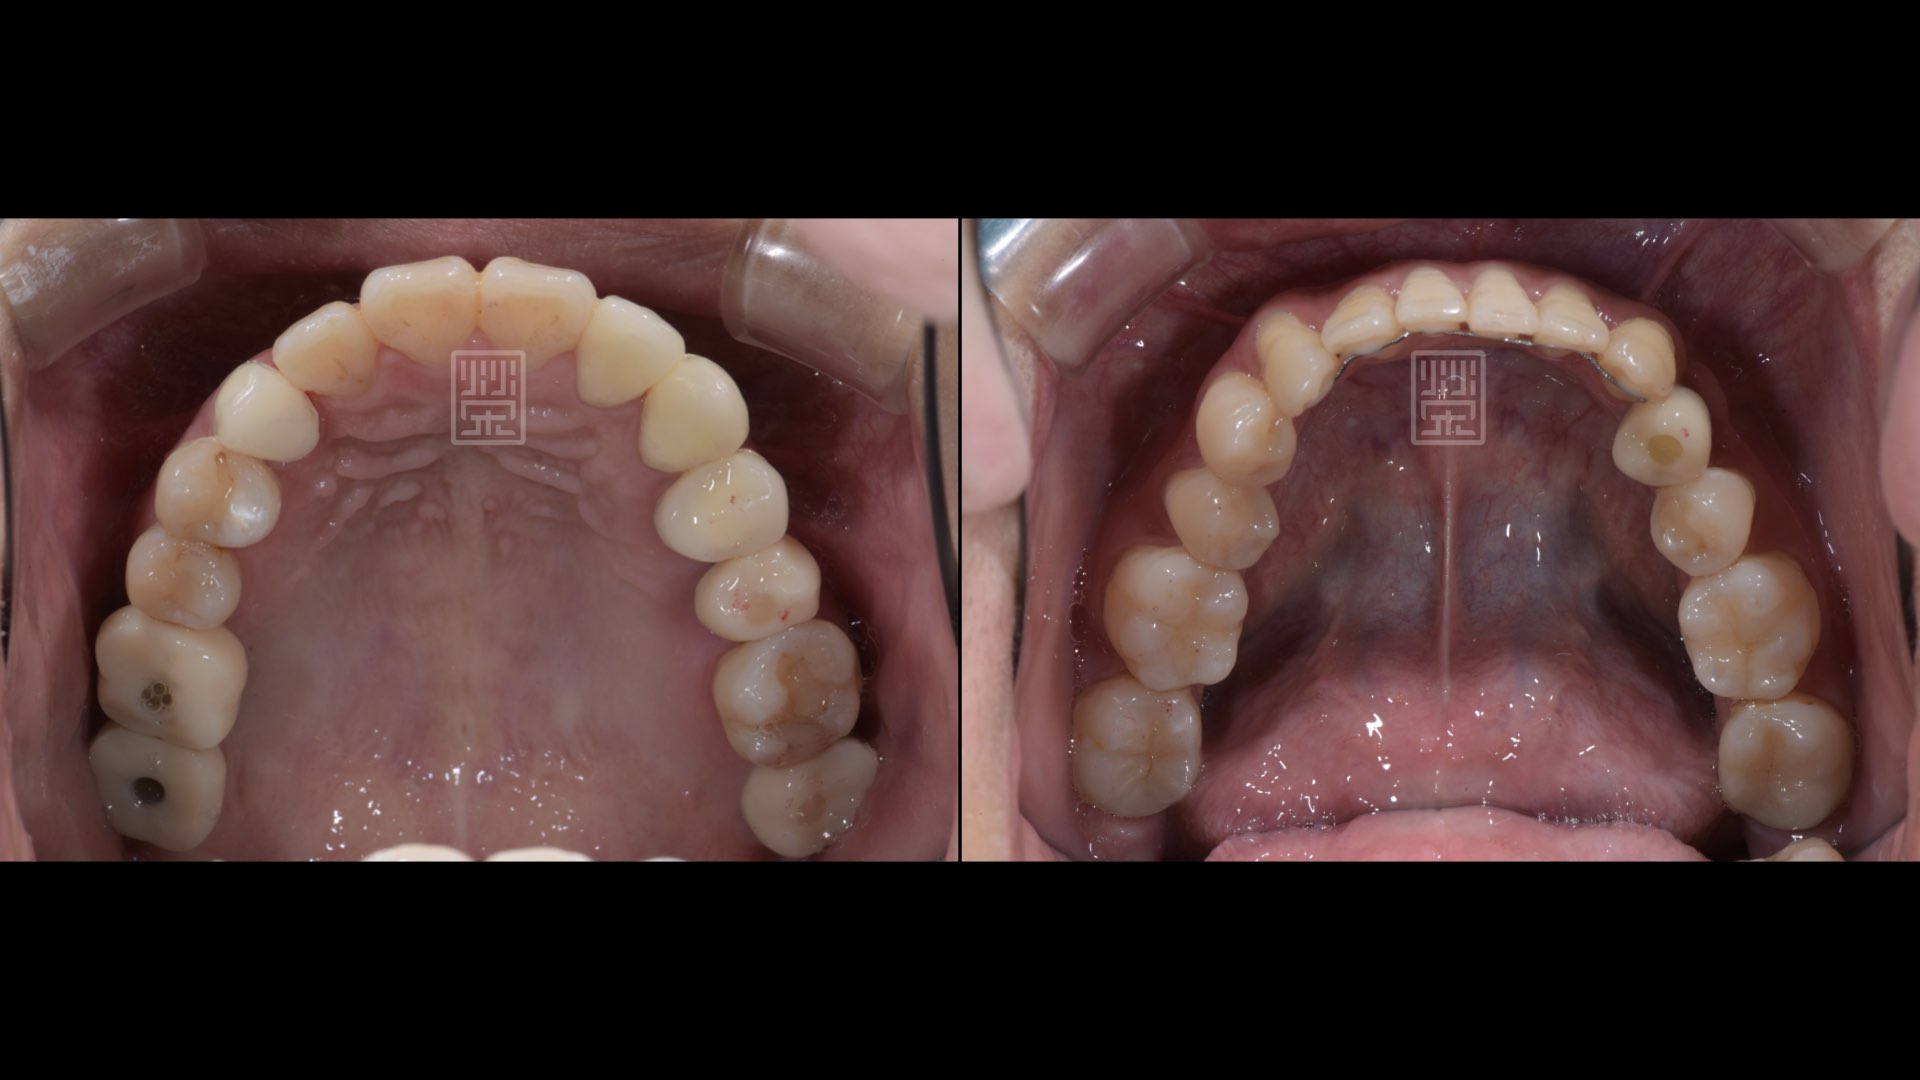

奈米樹脂、臨時假牙、植牙修復

全瓷冠、植牙修復完成